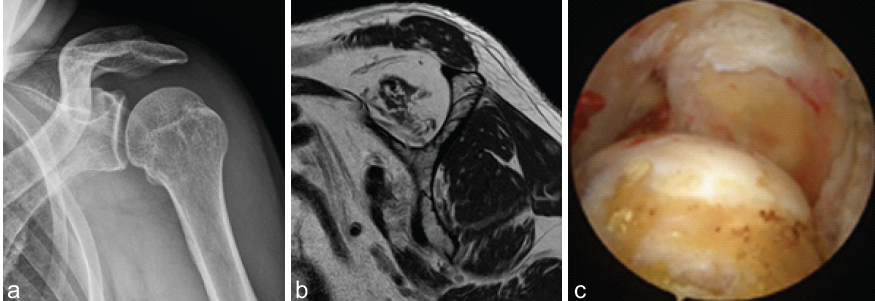

This case report reviewed the three one-arm patients who underwent aLDTM tendon transfer for ASIRCTs between 2020 and 2022 (minimum 2 years follow-up). One-arm patients were defined as those who rely on the ipsilateral arm due to a non-functional contralateral upper limb, which is limited in daily activities due to conditions such as amputation, palsy, or paralysis. Written informed consent was obtained from the patients. The criteria used to diagnose ASIRCTs included: (1) extensive rotator cuff tears involving both the subscapularis and supraspinatus tendons; (2) substantial tendon retraction and shortening to the level of the glenoid, corresponding to Patte stage III on magnetic resonance imaging (MRI); (3) advanced fatty degeneration in the affected tendons, classified as Goutallier grade 3 or 4; (4) a structurally preserved or reparable infraspinatus tendon with Goutallier grade 2 or lower; and (5) intraoperative confirmation that tendon mobilization was insufficient to allow reattachment to the humeral head footprint, even after thorough soft-tissue release (Fig. 1).

Figure 1: The diagnosis of anterosuperior irreparable rotator cuff tears. (a) An anteroposterior plane radiograph of the left shoulder shows minimal arthritis in the left shoulder joint (Hamada I). (b) A pre-operative T1-weighted oblique magnetic resonance imaging of the left shoulder demonstrates severe fatty infiltration of the subscapularis and supraspinatus tendons. (c) A diagnostic arthroscopic image of the left shoulder indicates relatively intact glenoid and humeral cartilage, and an empty footprint of the subscapularis and supraspinatus.